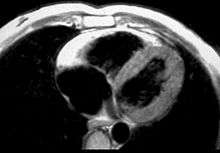

In vitro MRI and corresponding cross section of the heart in ARVD show RV dilatation with anterior and posterior aneurysms (17-year-old asymptomatic male athlete who died suddenly during a soccer game).

Fatty infiltration of the RV free wall can be visible on cardiac MRI. Fat has increased intensity in T1-weighted images. However, it may be difficult to differentiate intramyocardial fat and the epicardial fat that is commonly seen adjacent to the normal heart. Also, the sub-tricuspid region may be difficult to distinguish from the atrioventricular sulcus, which is rich in fat.

Cardiac MRI can visualize the extreme thinning and akinesis of the RV free wall. However, the normal RV free wall may be about 3 mm thick, making the test less sensitive.